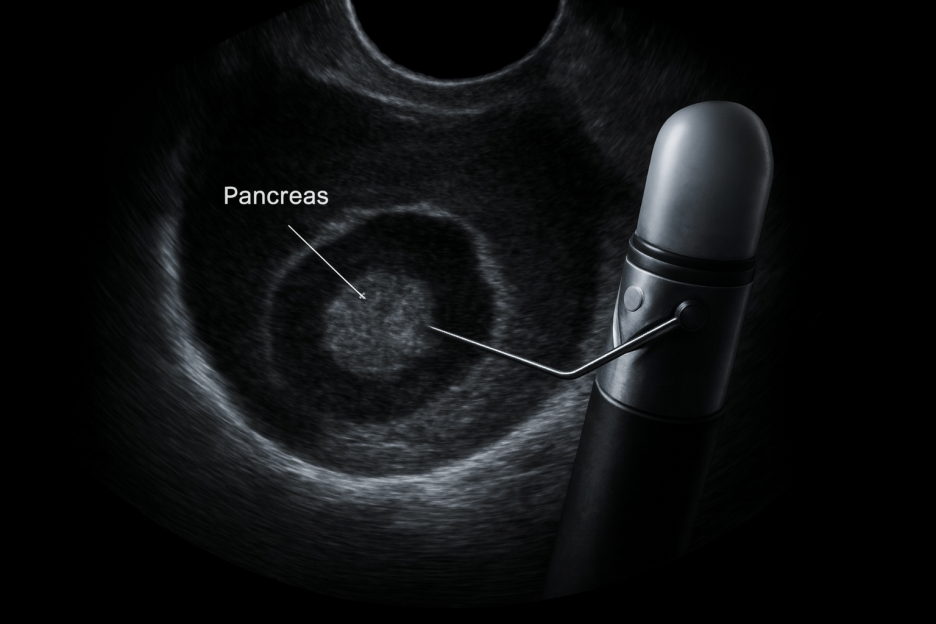

EUS 검사는 내시경 끝에 초음파 탐촉자를 장착해 몸속에 삽입한 뒤,

내시경 카메라로 장기의 내부를 확인하면서 초음파로 내부 조직의 단면까지 함께 촬영합니다.

2. 세침흡인검사(EUS-FNA)

초음파 유도하에 가는 바늘을 삽입해 조직이나 세포를 직접 채취합니다.